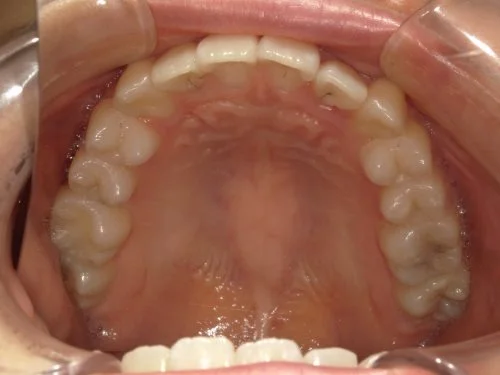

<症例7>歯がガタガタで噛み合わせが悪くお悩み

抜歯無し・マウスピースのみで矯正した症例です。

もともと歯列弓が非常に狭く、V字に近い形をしていたので噛み合わせも非常に不安定でした。

また、下顎前歯部がかなり上の方に生えていたため、下の前歯が上の前歯を突き上げてしまい出っ歯の状態になっていました。

現在では見た目はもちろん、臼歯の噛み合わせも改善しております。

患者様と症状

主訴:歯のガタガタ、噛み合わせが悪い

性別・年齢:20代女性

問題点:叢生(重度)、V字歯列弓、ディープバイト

診断:前歯部の叢生を伴うアングルⅠ級、骨格性Ⅰ級の不正咬合

主なリスク:臼歯の移動に伴い一時的に咬合しにくくなる、歯肉退縮

症状:叢生(そうせい) 過蓋咬合(かがいこうごう)

治療内容

治療期間:1年10ヶ月

治療費用:990,000円(税込)

プラン:Full2プラン

抜歯:無し

治療前後の写真